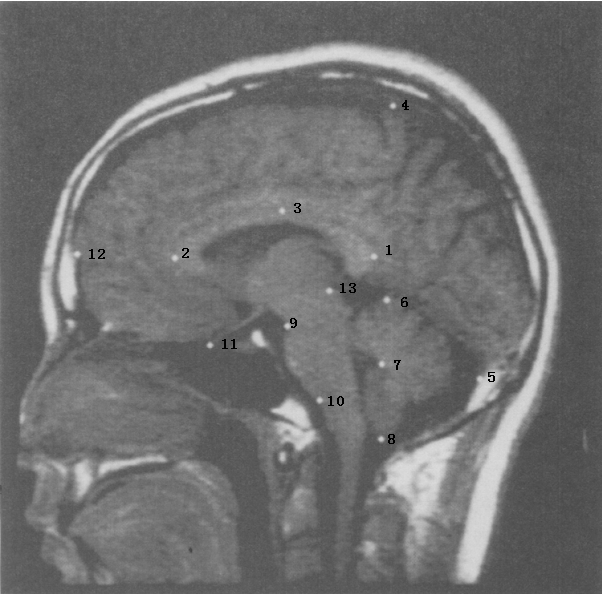

The global variable could be used to distinguish templates of different kinds, for example brains between humans and chimpanzees. In [7], we have utilized for clustering and classifying different simple contour curves. However, it may not be sensitive enough to compare subcategories of the same kind, such as brain structures between people with and without schizophrenia where only minor local changes could cause a difference. To distinguish such a difference, we need to resort to the local variable. In this section, we will focus on applying the residual momentum from Algorithm 1 for abnormality detection. A Bayesian predictive approach will be used to assess the information hidden behind the momentum representation . At the same time, we will discuss advantages of using the momentum representation over the traditional location representation. In order to justify this advantage numerically, we use a dataset of 28 parasagittal brain images for illustration. Each image is annotated by 13 landmarks. The dataset can be sorted into two groups. One contains 14 images of non-schizophrenic people, while the other has 14 images from confirmed schizophrenic cases. For more details about this dataset, we refer the reader to the link [16]. The annotated landmarks of a typical brain image in this dataset are shown in Figure 7. In applications like this, observations on landmarks of different individuals are essentially close, so we can expect the convergence of Algorithm 1.

4.1. Detection

For each image in the dataset, the annotated landmarks represent locations of human brain structures. It is well known that landmark locations could be different between a schizophrenic and a non-schizophrenic template. Such differences are sometimes beyond visualization and can only be identified through mathematical and statistical analysis. These landmarks carry certain features and information that can help distinguish schizophrenic images from a group of non-schizophrenic templates. We refer to the collection of these landmarks as a predictor. A predictor is viewed as a signature for describing the difference between templates. For the remainder of this section, we focus on finding the landmarks that comprise a predictor for our image data. The upshot of this exercise could help medical researchers locate those specific landmarks (structures of brain), and shed light on the development of the disease.

It is worth noting that in order to obtain convincing results, more than one method should be applied for validation. One of the traditional Procrustes methods uses superposition of datasets to compare the variations for each landmark. Adopting this approach, Bookstein[4] showed that landmarks 1 and 13 are the “most different” landmarks between the two groups in the dataset. For comparison, below we apply Algorithm 1 and use a Bayesian approach on momentum coordinates of each template to detect the abnormal landmarks.